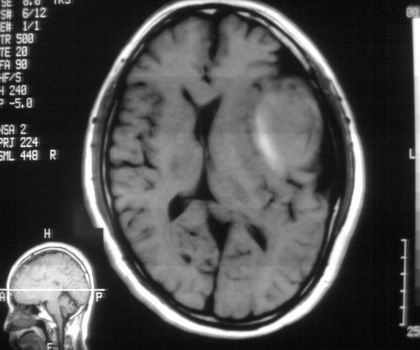

以下是引用影像孺子牛在2008-4-29 21:20:00的发言:[br]首先病变定位在脑外,根据ct密度及mri信号特征考虑慢性硬膜下血肿不连续环形钙化。

以下是引用周战梅在2008-4-29 23:12:00的发言:[br]脑外病变,蛛网膜下腔增宽,囊壁点状、环形钙化,增强扫描呈不均匀环状强化,考虑为囊性脑膜瘤可能性大,慢性脓肿、血肿机化、胆脂瘤不能除外。